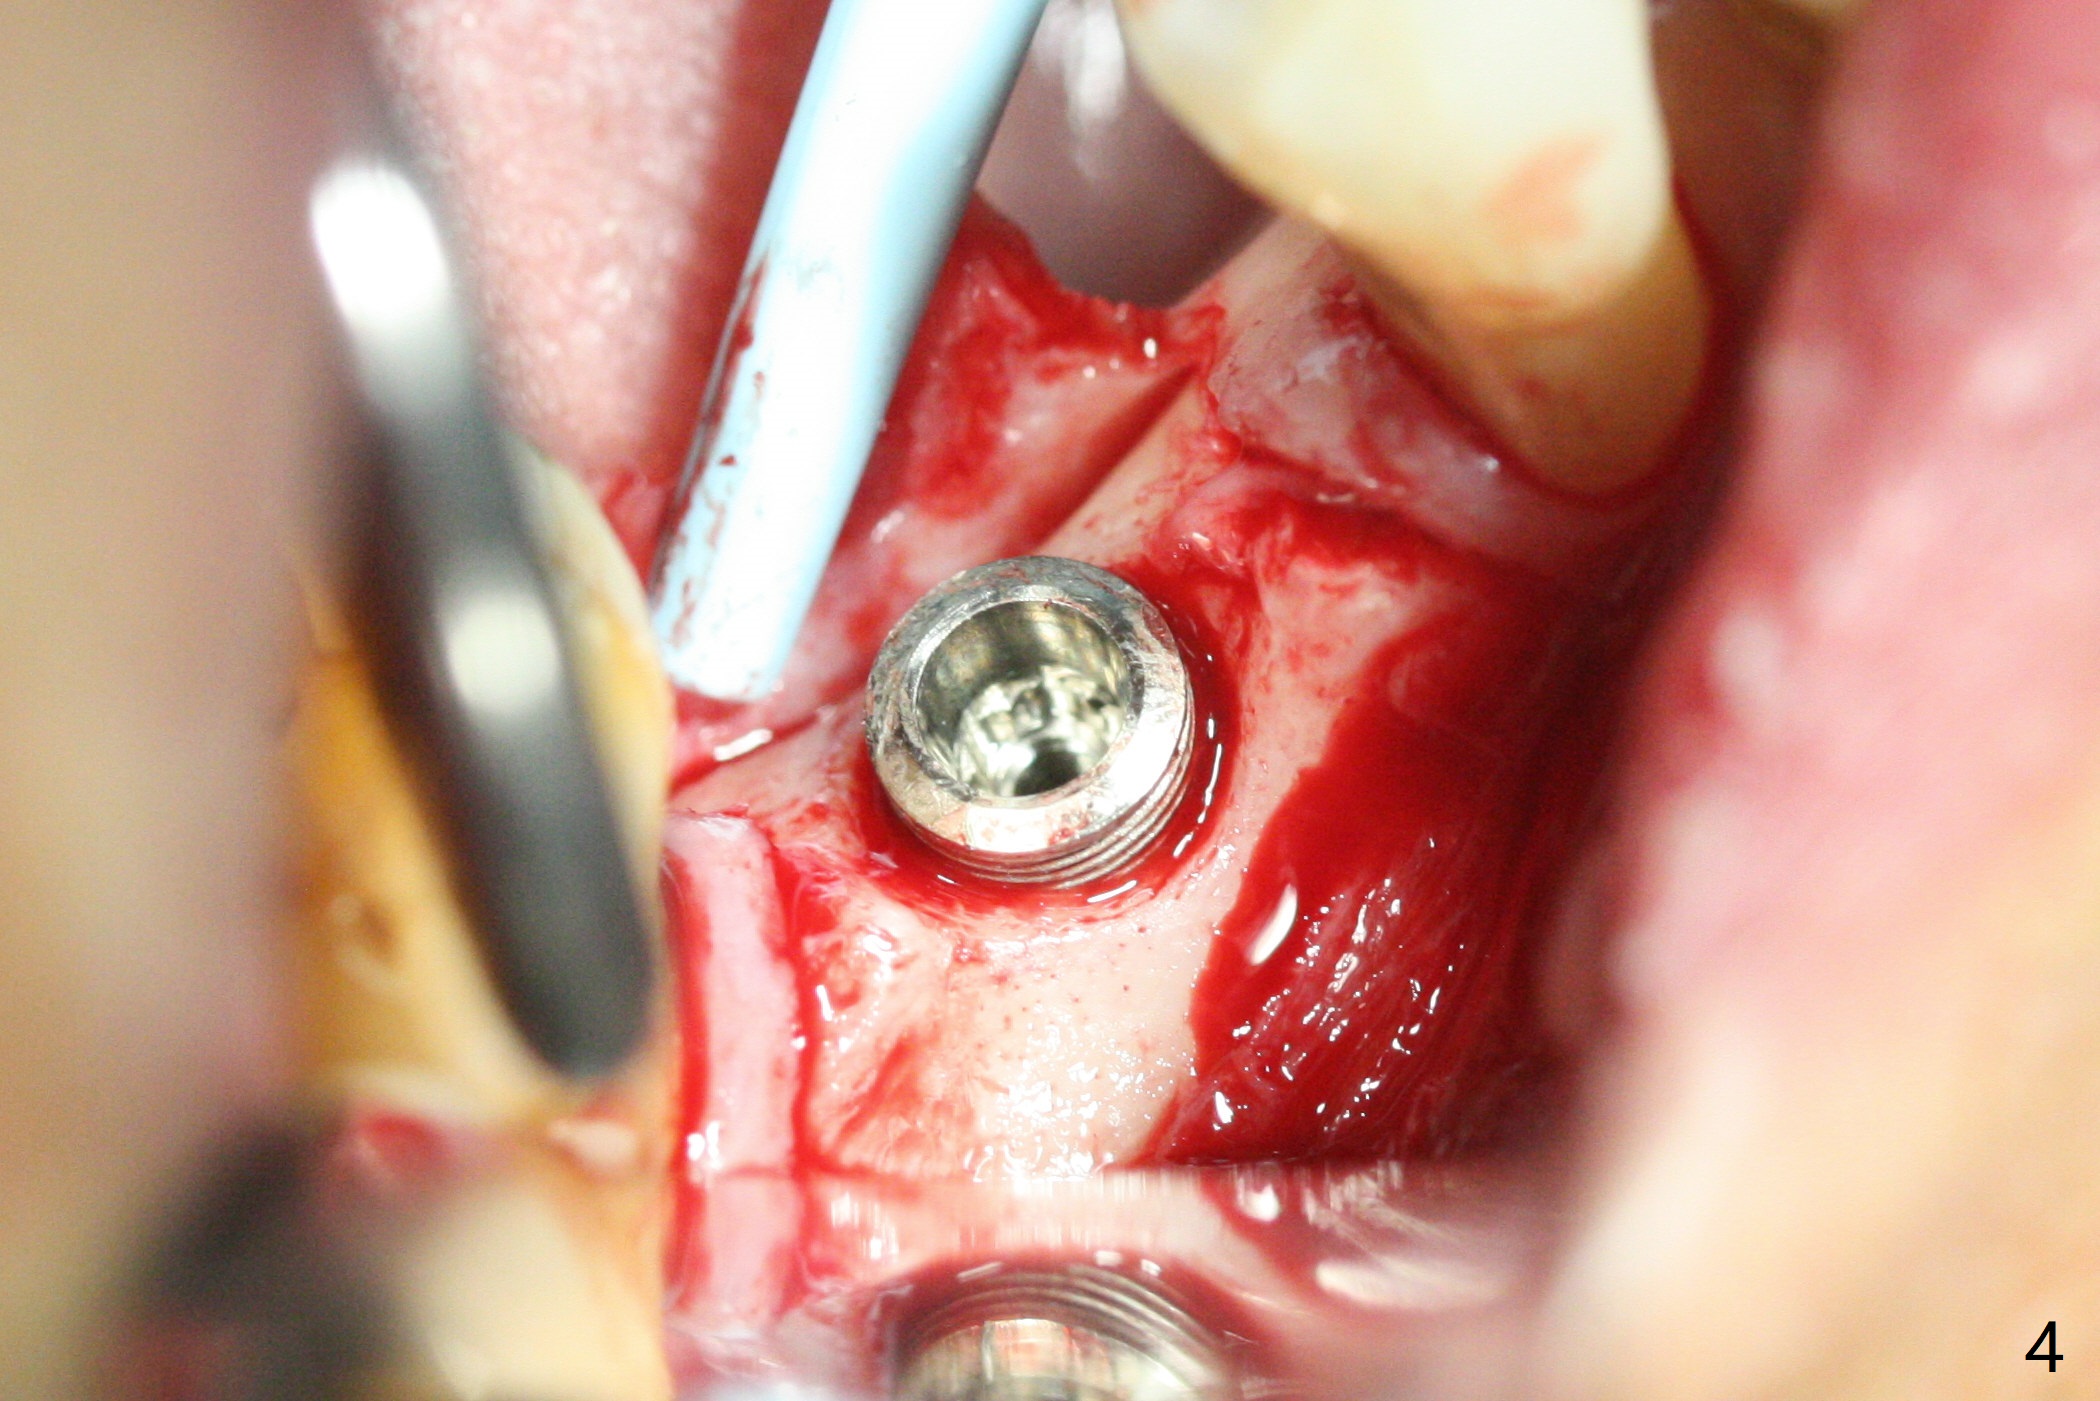

A 64-year-old man returns with history of a lump in the right submandibular region. Biopsy in a medical clinic shows inflammation. The implant crown at #30 has been cemented for ~ 4 years (Fig.1 (A: abutment)). The lingual plateau of the implant is exposed for 1-2 years asymptomatic (Fig.2 *). There is no deep lingual pocket when the crown and abutment are removed (Fig.3). Flap surgery confirms microthread exposure (circumferential, Fig.4). After removal of the microthreads with diamond bur (Fig.5), allograft (Fig.6 *), 6-month collagen membrane and a 6.5x5(3) mm healing abutment are placed. Following suturing, periodontal dressing is applied. The site remains asymptomatic 3 months postop, when an implant is placed subcrestal at #3.